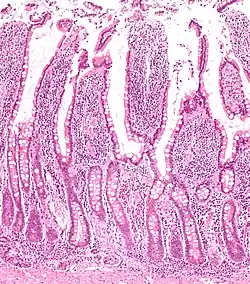

Histologisches Präparat der Dünndarmmukosa dargestellt sind die intestinalen Villi mit den Lieberkühnschen Krypten.

Lieberkühn-Krypten (lat.: Glandulae intestinales), auch bekannt als Darmdrüsen, Lieberkühn-Drüsen sowie Cryptae intestinales, sind etwa 0,2 bis 0,4 mm tiefe schlauchförmige, teilweise verzweigte Einsenkungen des Epithels im Bereich der Schleimhaut des Dünn- und Dickdarms. Benannt wurden sie nach dem Berliner Arzt und Anatomen Johann Nathanael Lieberkühn (1711–1756).